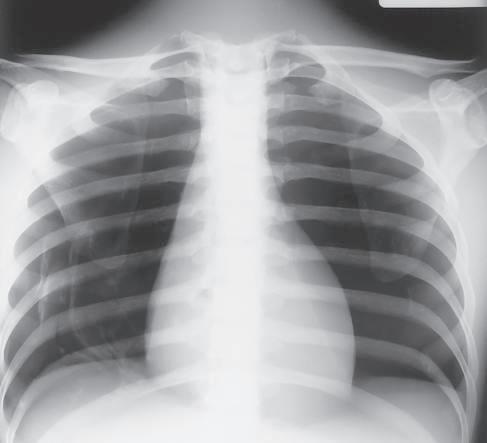

Definition Radiographic contrast is defined as the difference in density between adjacent areas of a radiographic image. When the density difference is large, the contrast is high and when the density difference is small, the contrast is low. This is demonstrated by the step wedge and by the chest radiograph in Fig. 1-126, which shows greater differences in density between adjacent areas; thus, this would be high contrast. Fig. 1-127 shows low contrast with less difference in density on adjacent areas of the step wedge and the associated radiograph.

Contrast can be described as long-scale or short-scale contrast, referring to the total range of optical densities from the lightest to the darkest part of the radiographic image. This is also demonstrated in Fig. 1-126, which shows short-scale/high-contrast (greater differences in adjacent densities and fewer visible density steps), compared with Fig. 1-127, which illustrates long-scale/ low-contrast.

Low or high contrast is not good or bad by itself. For example, low contrast (long-scale contrast) is desirable on radiographic images of the chest. Many shades of gray are required for visualization of fine lung markings, as is illustrated by the two chest radiographs in Figs. 1-126 and 1-127. The low-contrast (long-scale contrast) image in Fig. 1-127 reveals more shades of gray, as evident by the faint outlines of vertebrae that are visible through the heart and the mediastinal structures. The shades of gray that outline the vertebrae are less visible through the heart and the mediastinum on the high-contrast chest radiograph shown in Fig. 1-126.

Fig. 1-126 High-contrast, short-scale 50 kV, 800 mAs.